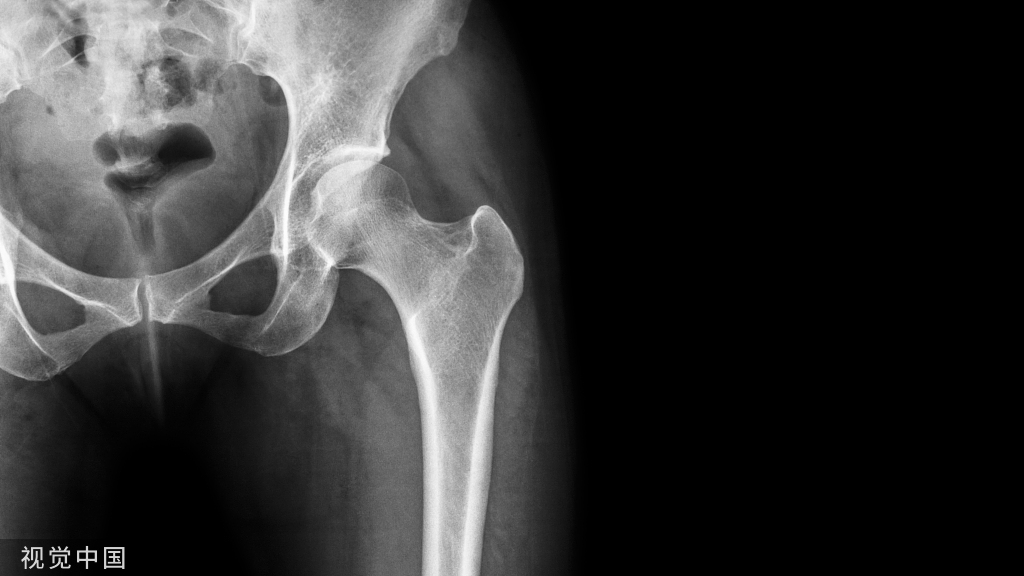

常规的膝关节周围截骨术主要包括胫骨高位截骨术(HTO)和股骨远端截骨术(DFO)。

图2 股骨远端截骨术(DFO)